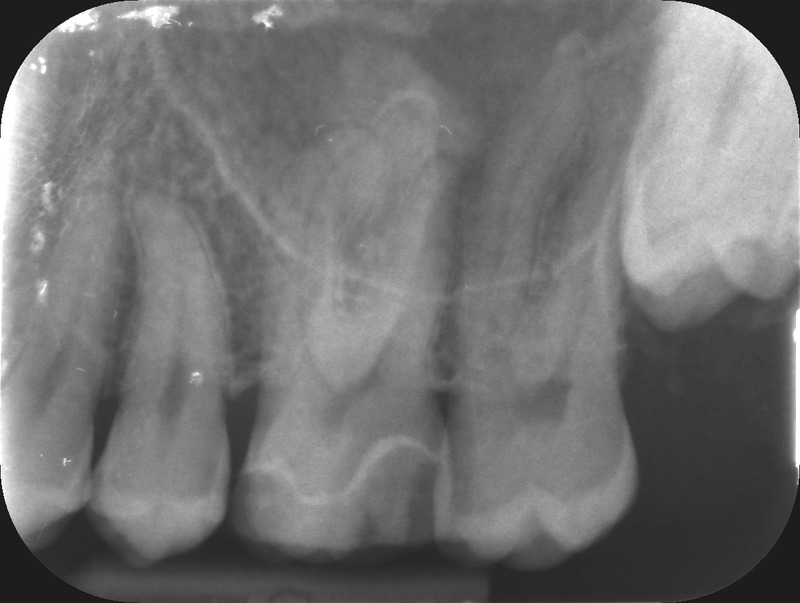

Dental trauma management

Pre-operative photo and X-ray